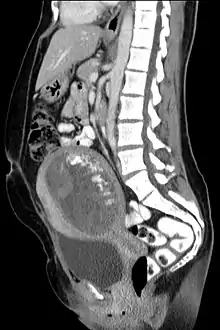

Hydatidiform mole on CT, sagittal view

The diagnosis is strongly suggested by ultrasound (sonogram), but definitive diagnosis requires histopathological examination. On ultrasound, the mole resembles a bunch of grapes ("cluster of grapes" or "honeycombed uterus" or "snow-storm").[14] There is increased trophoblast proliferation and enlarging of the chorionic villi, and angiogenesis in the trophoblasts is impaired.[15]